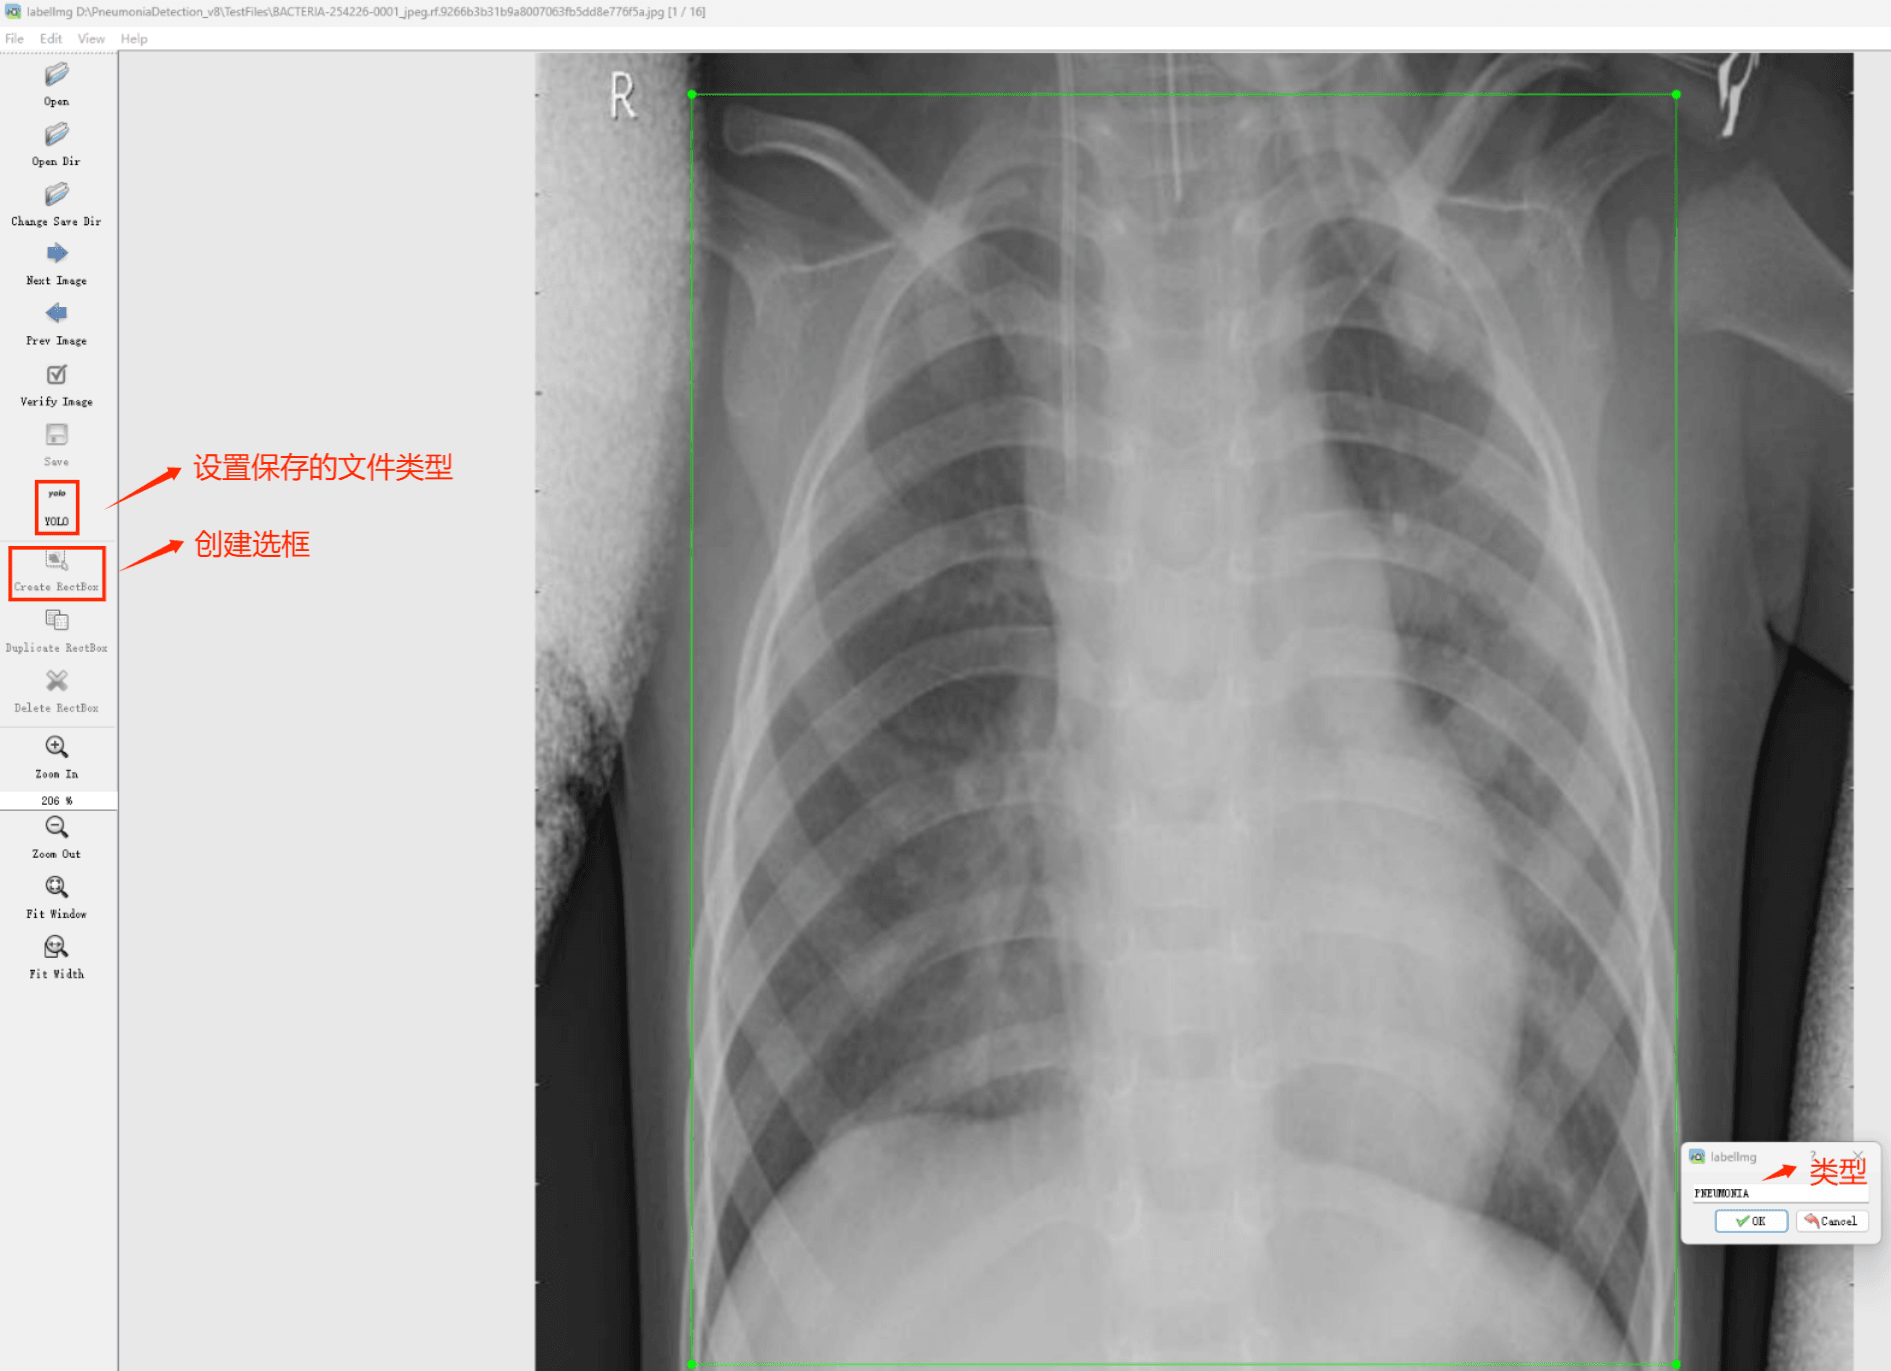

目标检测标注工具

(1)labelimg:开源的图像标注工具,标签可用于分类和目标检测,它是用python写的,并使用Qt作为其图形界面,简单好用(虽然是英文版的)。其注释以 PASCAL VOC格式保存为XML文件,这是ImageNet使用的格式。此外,它还支持 COCO数据集格式。

初识labelimg

打开后,我们自己设置一下

在View中勾选Auto Save mode

接下来我们打开需要标注的图片文件夹

并设置标注文件保存的目录(上图中的Change Save Dir)

接下来就开始标注,画框,标记目标的label,然后d切换到下一张继续标注,不断重复重复。

(4)YOLO模式创建标签的样式

存放标签信息的文件的文件名为与图片名相同,内容由N行5列数据组成。

每一行代表标注的一个目标,通常包括五个数据,从左到右依次为:类别id、x_center、y_center、width、height。